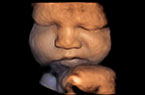

Face foetale en 3D, pivotante Visage lunaire  lunaire pivotante : 37 SA